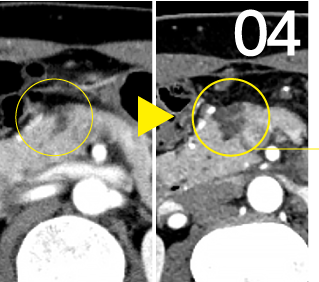

当院が行っている工夫の膵嚢胞事例です。膵臓がんに向かう途上で確認されることの多い画像所見膵嚢胞(IPMN含)

2021年

2月健診超音波検査にて膵嚢胞が指摘され、MRIによる追加検査を実施。膵体部に膵嚢胞を指摘。 -

2022年

8月やや悪化膵嚢胞がはっきりと見えるようになり、サイズがやや大きくなっている可能性があります。 -

2023年

11月更に悪化更にはっきりと見える嚢胞や、初回検査に比べサイズが大きくなったものも指摘されます。

2022年8月にはやや悪化、2023年11月には顕著に悪化したことで膵臓がんの可能性を考えました。 -